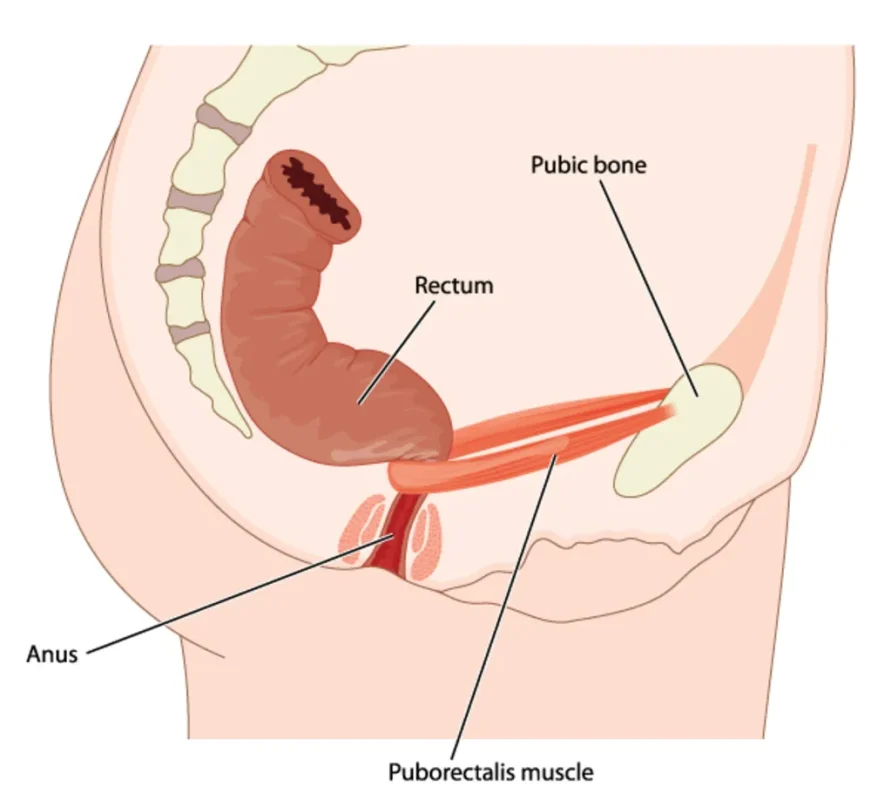

ناحیه مقعد (Anus) بهعنوان انتهاییترین بخش دستگاه گوارش، مسئول انجام یکی از مهمترین و در عین حال پیچیدهترین فرآیندهای فیزیولوژیک بدن یعنی دفع مواد زائد است. این ناحیه برخلاف تصور رایج، تنها یک خروجی ساده محسوب نمیشود؛ بلکه یک واحد عملکردی و عصبی-عضلانی بسیار دقیق است که در هماهنگی کامل با بخشهای فوقانی سیستم گوارش، نقش مهمی در حفظ تعادل بدن، دفع مؤثر و کنترل بیاختیاری ایفا میکند.

ساختار عملکردی ناحیه مقعد

از نظر عملکردی، ناحیه مقعد به مجموعهای از ساختارهای بافتی، عضلانی و عصبی اطلاق میشود که در کنار یکدیگر، شرایط لازم برای کنترل دقیق عمل دفع را فراهم میسازند. این ساختارها عبارتاند از:

- کانال آنال (Anal Canal)

- عضلات اسفنکتر داخلی و خارجی

- عروق هموروئیدی

- گیرندههای حسی و شبکه عصبی محیطی

- عضلات کف لگن و دیافراگم لگنی

عملکرد طبیعی ناحیه مقعد در گرو همکاری کامل این اجزا و پاسخ هماهنگ به تحریکات فیزیکی و عصبی است.

نقش ناحیه مقعد در انتهای سیستم گوارشی

پس از اتمام فرایندهای گوارشی در معده و رودهها، مواد زائد و غیرقابل جذب به صورت مدفوع وارد راستروده (رکتوم) میشوند. رکتوم بهعنوان مخزن موقت مدفوع عمل کرده و به محض پر شدن، سیگنالهای عصبی خاصی از طریق گیرندههای کششی به مغز ارسال میشود. این سیگنالها مرکز عصبی کنترل دفع را فعال کرده و فرآیند دفع را آغاز میکنند.